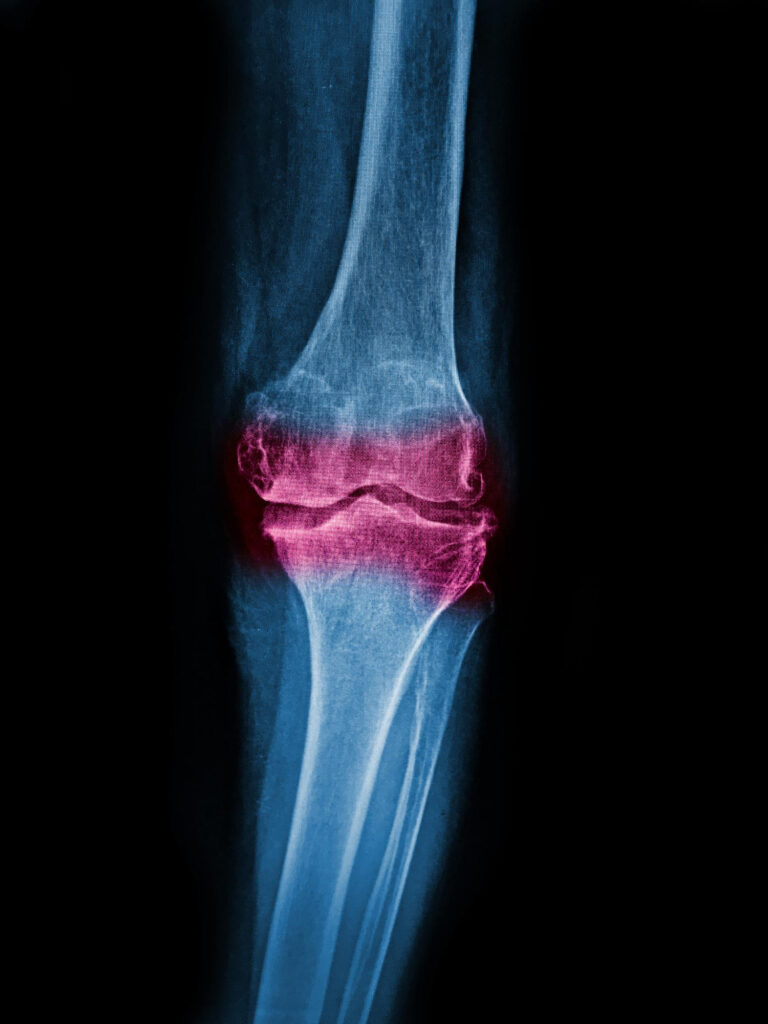

Our breakthrough approach uses advanced technology, including the knee traction machine, to gently stretch and decompress the knee joint. This process—known as knee decompression therapy—helps increase joint space, improve circulation, reduce inflammation, and promote natural healing within the knee. If you’ve been searching for knee decompression therapy near me, our chiropractic wellness center offers one of the safest and most effective options available today.

This FDA-cleared therapy has shown remarkable success in helping those with:

Bone spurs

Degenerative arthritis

Post-injury or trauma-related knee pain

Chronic inflammation and stiffness

Knee pain can be quite debilitating, as it is one of the most used and complex joints of the human body. The stability of the knee is due to four ligaments, muscles and the actual joint structure. During the course of a normal day, the knee goes through a whole range of motions, from sitting, walking, twisting etc.

The knee also supports out weight in conjunction to the feet. Because of the abuse we put our knees through there can be damage to the muscle, cartilage or the joint itself. Some of the pain can be alleviated with the use of anti-inflammatory ointments or tablets, more severe cases need medical attention for a more effective treatment while some patients have even had their knee or knees replaced.